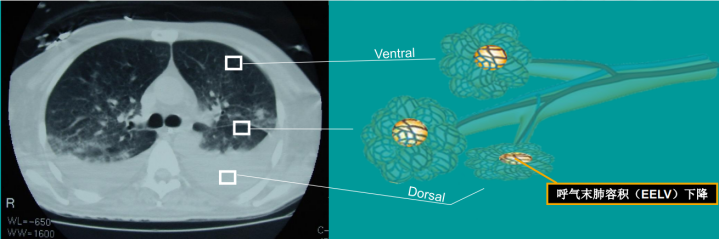

下图是非常典型的ARDS影像学,在下肺可见实变和塌陷区域,呼气末肺容积明显减少。

图片

对于正常或者过度通气的区域,给予小潮气量通气,同时给予一个合适的PEEP,对于一些塌陷的肺单元,包括小气道塌陷引起的疏松性肺不张和肺单元内气体被吸收后引起的黏性肺不张,都需要进行肺复张,使塌陷的肺泡开放,维持肺的通气状态。而对肺实变区域进行肺复张的效果并不好。